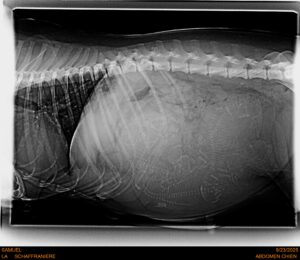

SAMU’ELLE on attend la mise bas milieu de la semaine prochaine, vraiment début octobre. 6 à 7 chiots!

RADIO DE SAMU’ELLE